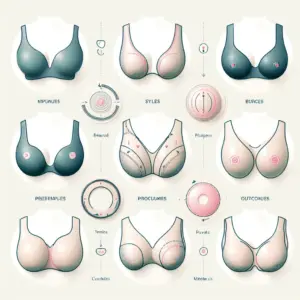

Qual a Melhor Cirurgia para Levantar as Mamas? Comparação Entre Técnicas e Resultados

A melhor cirurgia para levantar as mamas varia conforme o grau de ptose, volume e pele, com técnicas específicas para cada caso. Avaliação médica personalizada é essencial para resultados naturais e satisfatórios.